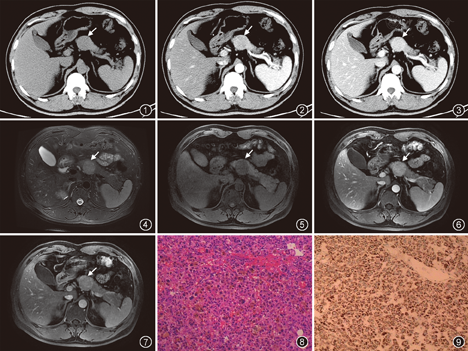

B超表现:胰腺颈部低回声类圆形肿块影,回声较均匀,边界清晰,可见包膜,肿块后方回声轻度增强。CT表现:平扫发现胰腺颈部稍低密度肿块影,边界清晰,直径3.2 cm,平均CT值为37 HU,肿块内部密度均匀,无钙化及出血征象(图1)。增强扫描动脉期肿块明显均匀强化,CT值为128 HU,肿块边界可见包膜环状强化(图2);门静脉期病灶进一步强化,CT值达137 HU,相对正常胰腺实质为高密度改变(图3)。胰腺体尾部实质密度均匀,病灶邻近的胰腺体部呈轻度萎缩改变,胰管未见明显扩张。MRI表现:脂肪抑制T2WI上肿块呈中等程度稍高信号改变,边界清晰,边缘见稍低信号包膜影,内部见点状更高信号影(图4)。肝脏快速容积采集平扫肿块呈稍低信号改变,肿块内部可见点状更低信号影(图5)。DWI上肿块呈稍高信号改变,表现为扩散中等程度受限。增强扫描动脉期肿块中等程度强化,病灶内部见点状更高强化,边缘包膜可见环状强化(图6);静脉期病灶进一步强化,病灶包膜环状强化更为明显(图7)。

手术及病理表现:术中胰腺颈部见一直径约3 cm肿块,表面光滑,周围组织无侵犯,与胰腺紧密粘连,术中肿块完全剥离。病理巨检,肿块为实性,较软,肿块有假包膜(受压的胰腺和纤维组织)。肿块切面呈灰黄色,可见局灶性出血,无坏死区。显微镜下,肿瘤细胞排列成条索状、板层结构,间质丰富可见血窦。肿瘤细胞呈多角形,胞质丰富,呈颗粒状,嗜伊红,细胞间隙见棕黄色素(图8)。免疫组织化学肝细胞石蜡抗原(HepPar1)在肿瘤细胞上呈阳性(图9)。癌胚抗原在肿瘤间质呈管状染色,CD34在肿瘤组织毛细血管呈阳性,CD56、CD99、CK8、CK18在肿瘤细胞胞质内呈阳性染色。突触素和嗜铬粒蛋白均为阴性。病理诊断为胰腺原发肝细胞癌。